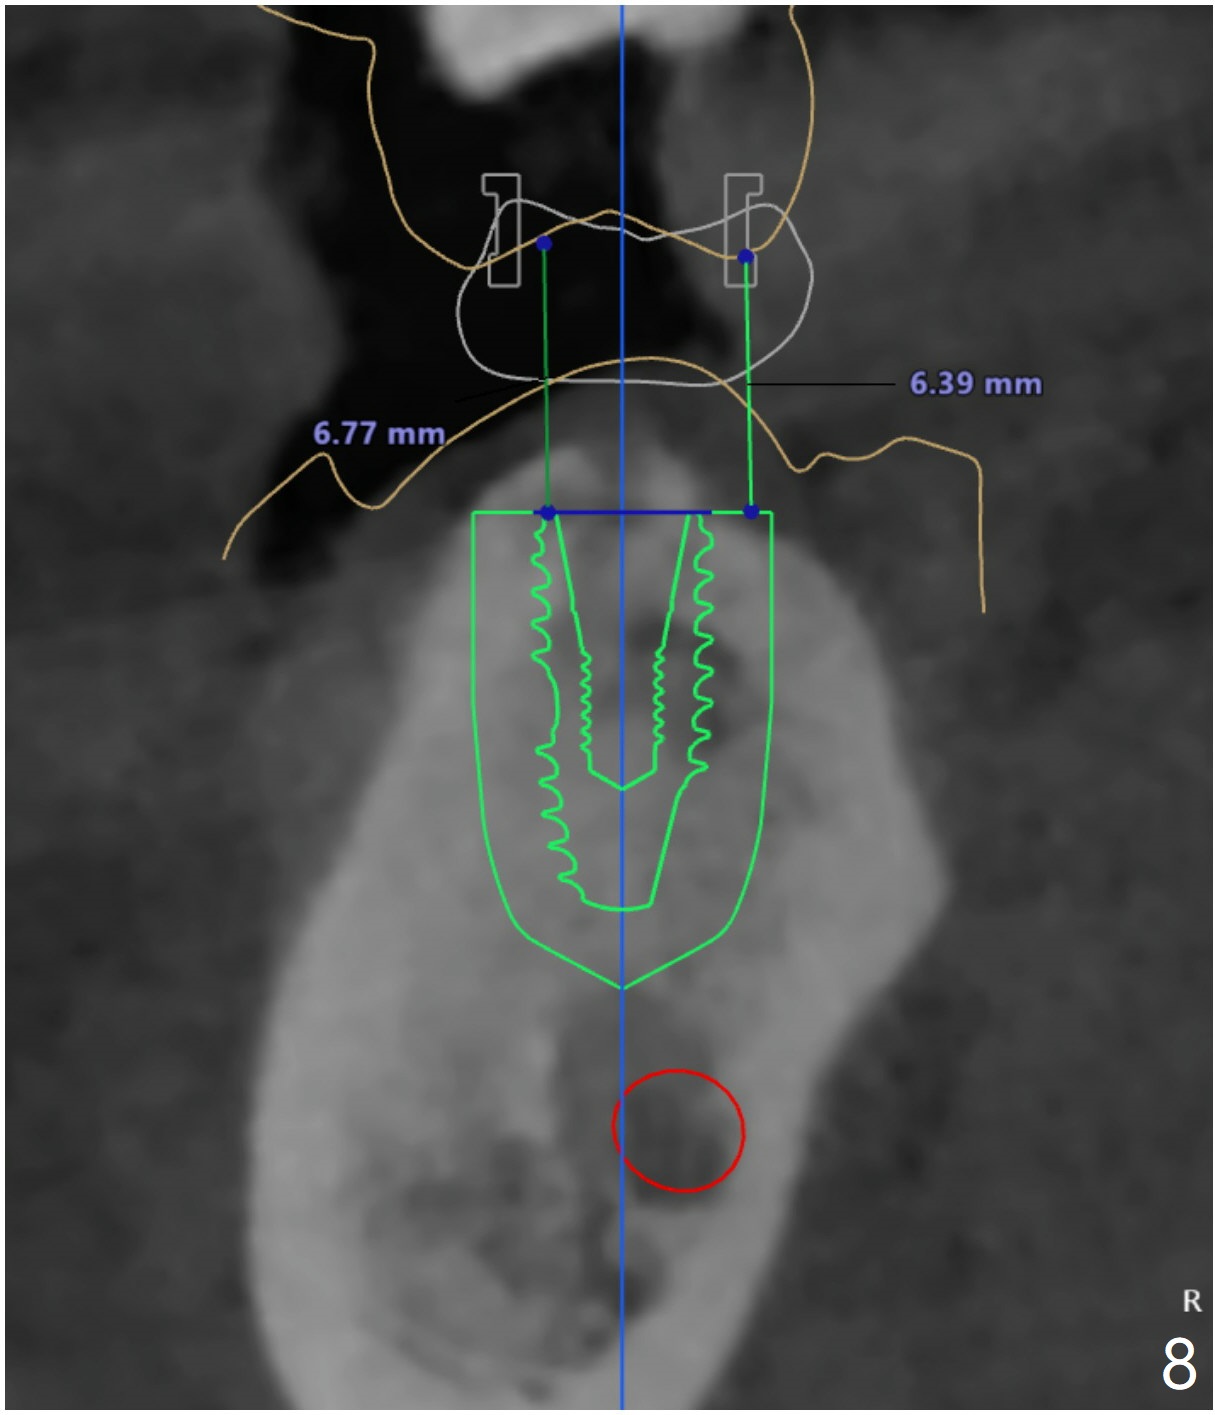

There is about 6mm of clearance between the supraerupted #2 and the implant platform (Fig.8). Barely enough. There is plenty of the apical bone at #30 (Fig.9). It is safe to place a 4.5x11 mm IBS implant. But the apical bone at #31 is not a lot. It is better to place 4.5x9 or 10 (UF?) mm implant at #31. If the bone density is not high at #24 (Fig.10), do not use the last drill fully.